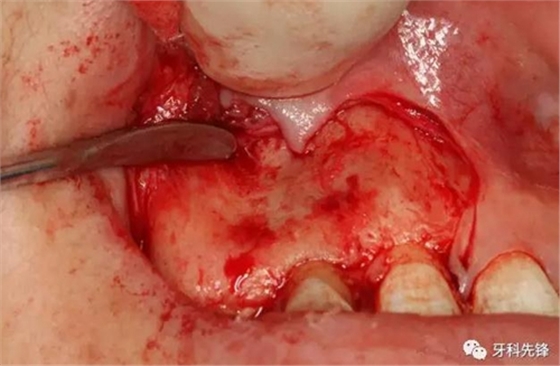

圖8.超聲骨刀去除囊腫上方的骨壁。

圖9.去除部分唇側(cè)骨板、顯露完整囊壁。

圖10.囊壁完整顯現(xiàn)。